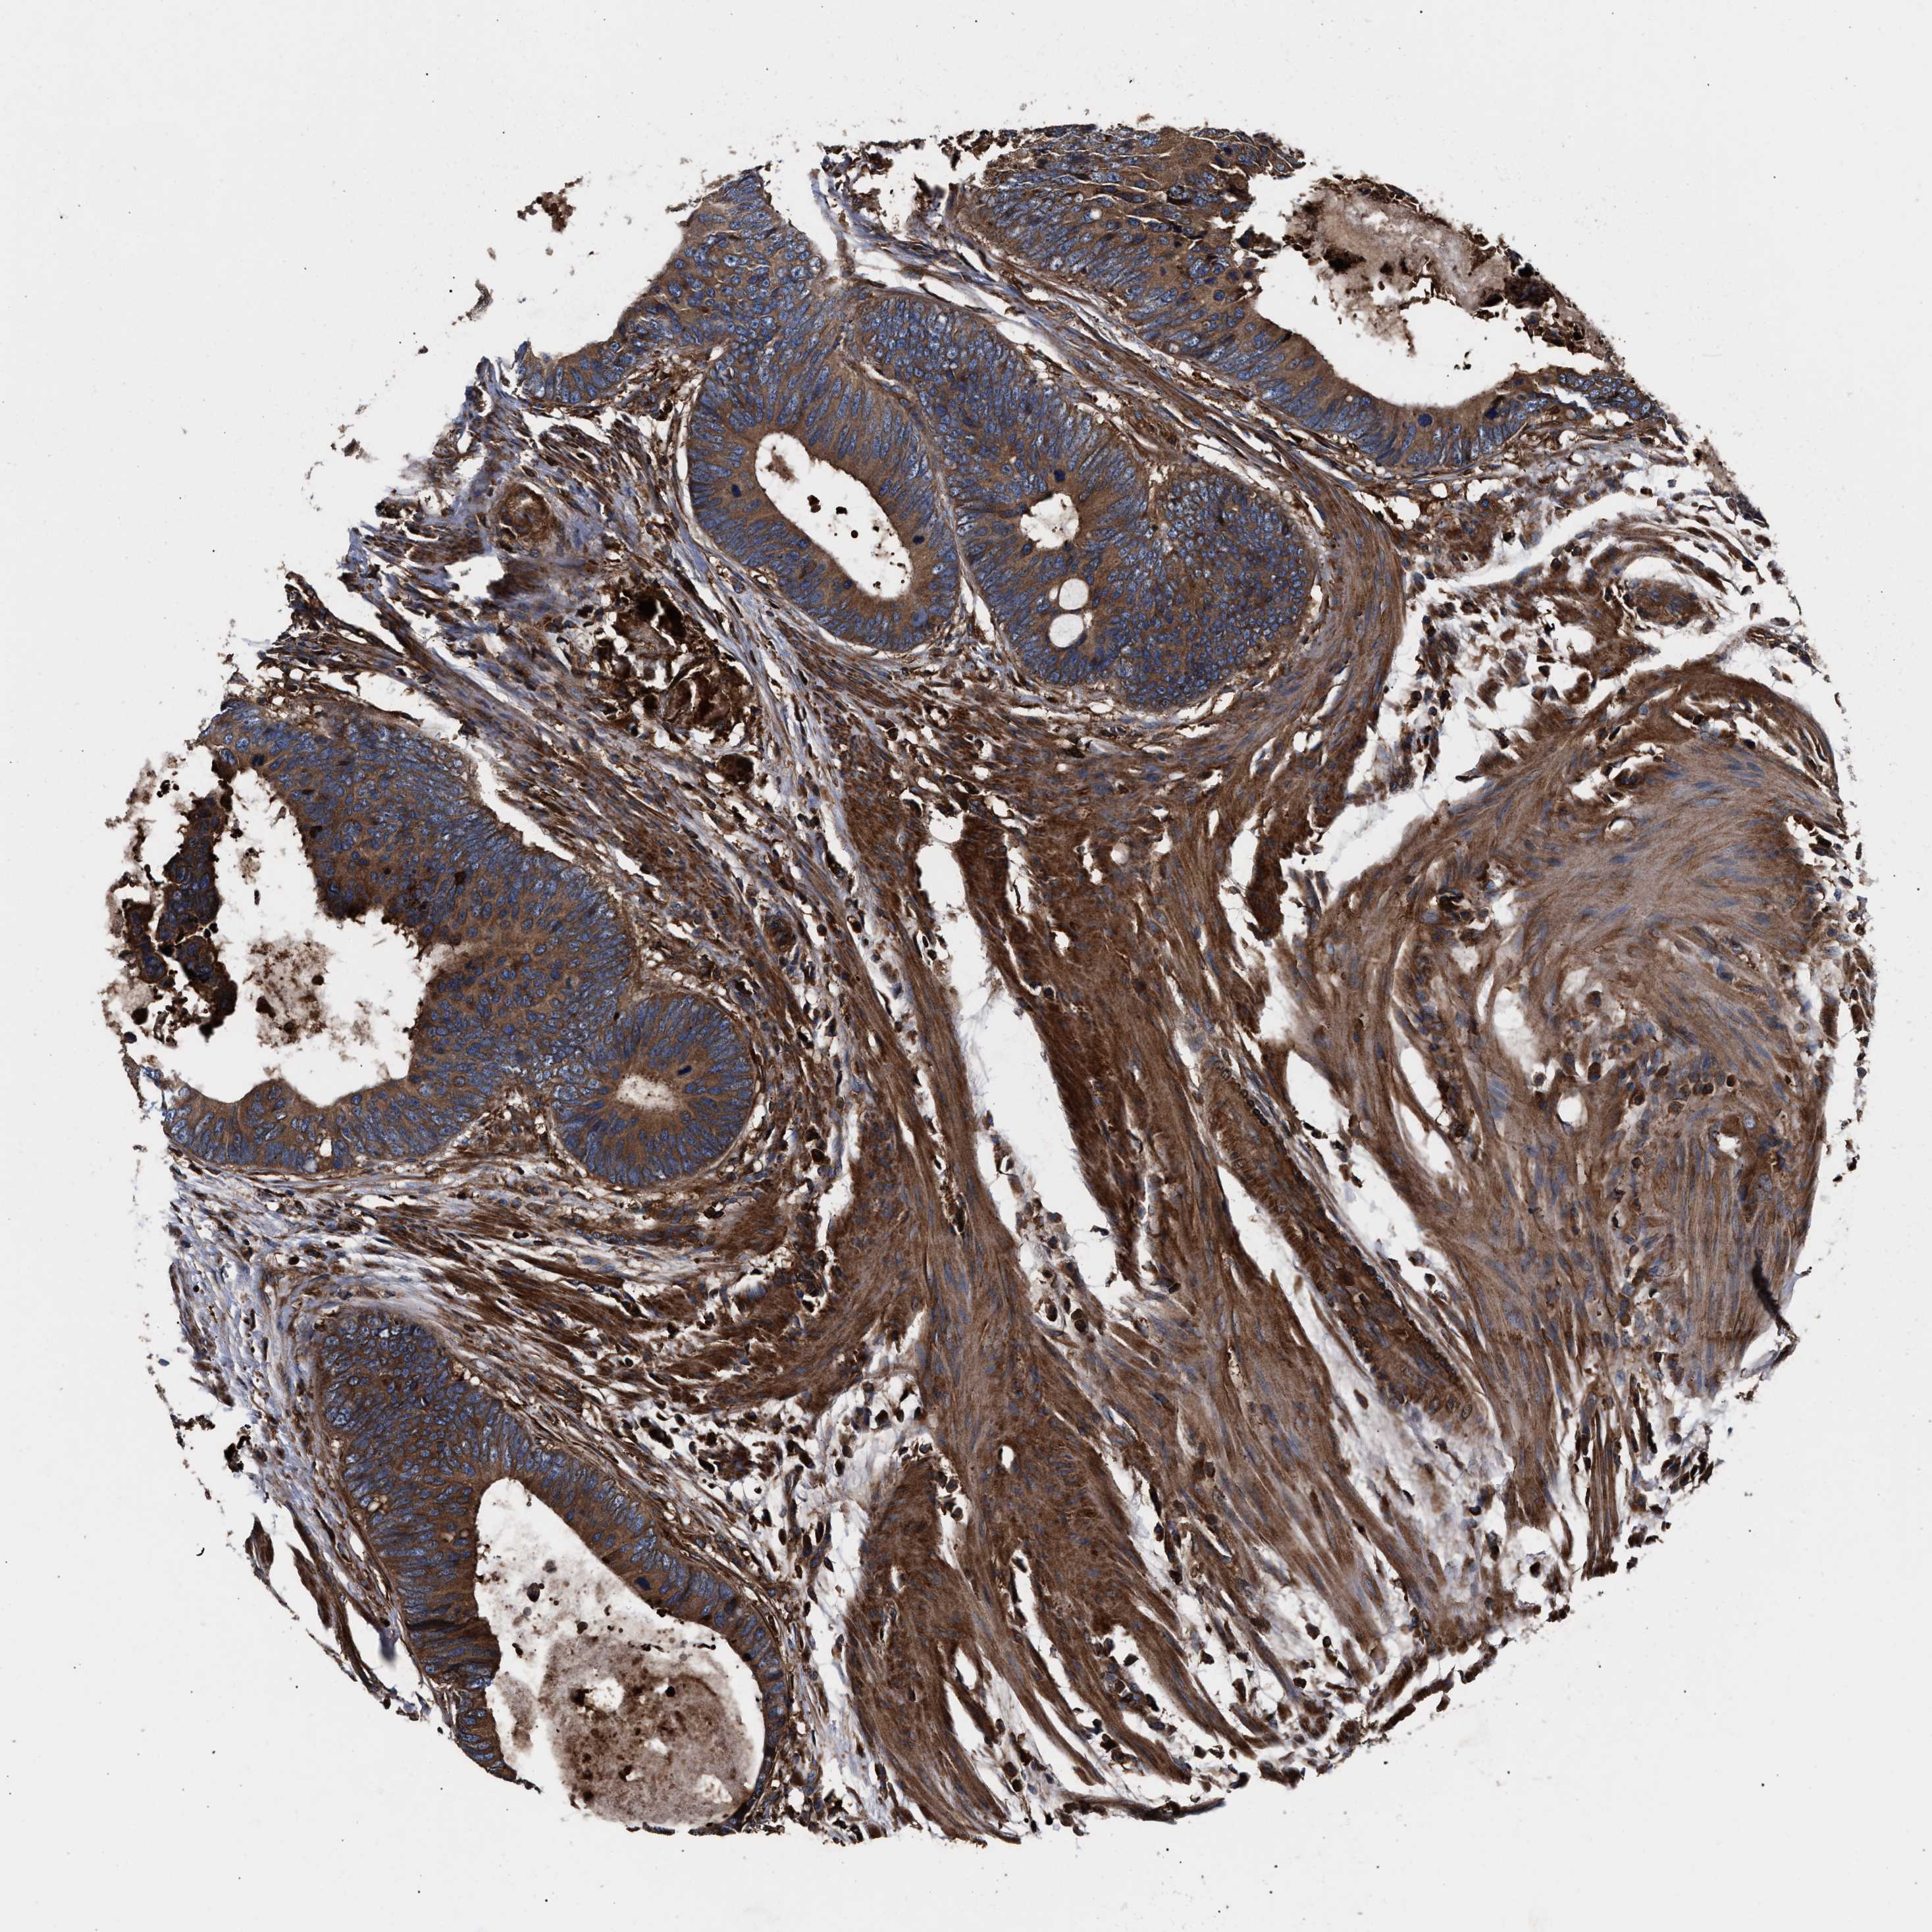

CANCER COLORECTAL CANCER Show tissue menu

Colorectal cancer

Human cancer

Colon adenocarcinoma

Rectum adenocarcinoma